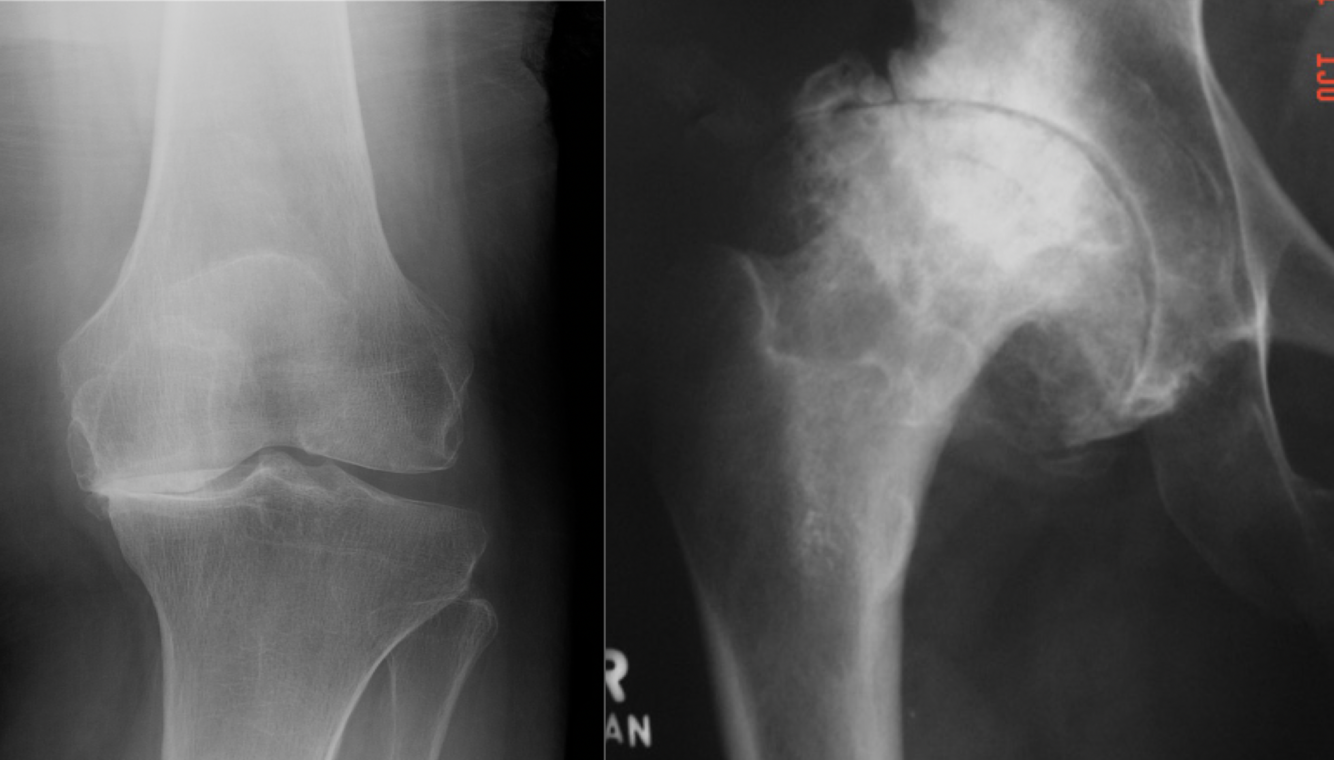

16

Q

Rx: atteinte mécanique vs inflammatoire

A

Mécanique: arthrose, usure asymétrique

Inflammatoire: atteinte concentrique diffuse

18

Inflammatoire vs mécanique

Gauche mécanique

Droite inflammatoire